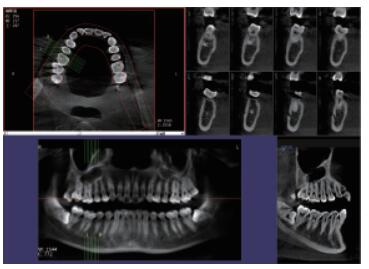

4、口腔CBCT(口腔CT)

CT相對其他牙片來講,不管是功能還是設備上都是比較高級的,醫生可在電腦上進行模擬種植360°的旋轉查看口腔狀況,不遺漏任何一個角落,主要用于根管治療前、阻生牙、根尖囊腫、種植牙、正畸等。

口腔CBCT三維影像